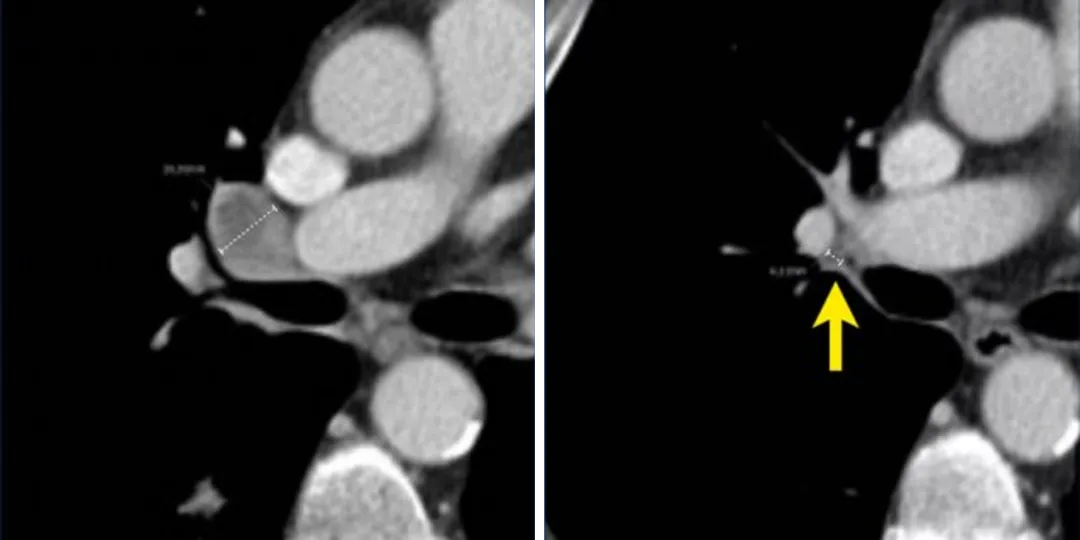

淋巴结靶病灶在基线时最长短径为18mm(左),在后续访视时减小到4mm(右),这时候仍须记录其实际测量数值,并将其计入靶病灶总和中,这样即使后续淋巴结再次出现肿大,我们也不会夸大其进展程度,而且即使淋巴结直径之和不为零,也可以达到完全缓解。